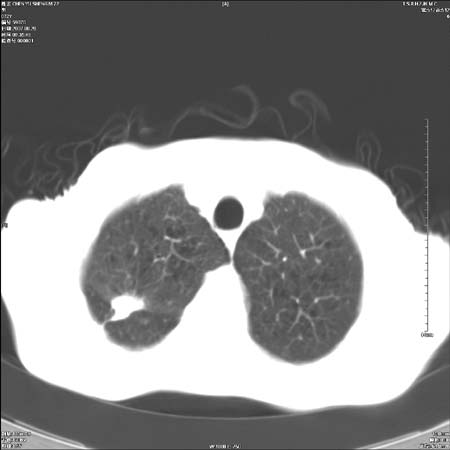

男性,72岁,既往肺结核,今复查。无前片对比。

纵隔窗

右侧中央型肺癌伴中叶不张可能性大,建议增强扫描.右上肺陈旧性肺结核.慢性支气管炎伴肺气肿.右侧少量胸腔积液.

右侧中央型肺癌伴中叶不张可能性大,建议纤支镜检查.右上肺陈旧性肺结核.肺气肿。

典型右肺中心型肺癌

右侧中央型肺癌伴肺不张可能性大,建议增强扫描.右上肺陈旧性肺结核.慢性支气管炎伴肺气肿.右侧少量胸腔积液.

右肺中心型肺癌

右侧中央型肺癌.上肺陈旧性肺结核.

1右侧中央型肺癌伴中叶不张2右侧少量胸腔积液3右上肺陈旧性肺结核

1.右肺中心性肺癌并右肺中叶综合征2。右侧胸腔少量积液3。右肺上叶结核球已钙化,4。慢支伴肺气肿

右侧中央型肺癌伴中叶不张可能性大,建议纤支镜检查.右上肺陈旧性肺结核.肺气肿。

右侧中央型肺癌伴中叶不张可能性大,建议增强扫描.右上肺陈旧性肺结核.慢性支气管炎伴肺气肿.右侧少量胸腔积液.

右侧中央型肺癌伴中叶不张

右肺中央型肺癌伴右肺中叶不张。

右上肺陈旧性肺结核。

支持右肺中心型肺癌并中叶不张,右上肺陈旧性肺结核钙化,右侧少量胸腔积液。

支持右侧中央型肺癌伴中叶不张可能性大,建议增强扫描.右上肺陈旧性肺结核.慢性支气管炎伴肺气肿.右侧少量胸腔积液.

支持 1右侧中心型肺癌伴中叶不张2右侧少量胸腔积液3右上肺陈旧性肺结核4双肺局限性肺气肿

1,右侧中央型肺癌.

2,右上肺陈旧性肺结核.

1.右侧中央型肺癌伴中叶不张,建议纤支镜检查.

2.右上肺陈旧性肺结核.

3.肺气肿。

4.右侧少量胸腔积液.

右侧中央型肺癌伴中叶不张并纵隔淋巴结增大,建议增强扫描.右上肺陈旧性肺结核.慢性支气管炎伴肺气肿.右侧少量胸腔积液。

右肺中心型肺癌并肺不张,陈旧性肺tb.慢支,肺气肿.

陈旧性肺结核.慢性支气管炎伴肺气肿,中央型肺癌伴中叶不张。

右侧中央型肺癌伴中叶不张可能性大;右上肺陈旧性肺结核.慢性支气管炎伴肺气肿

陈旧性结核是存在,但真正致命的却是右侧中心型肺癌。